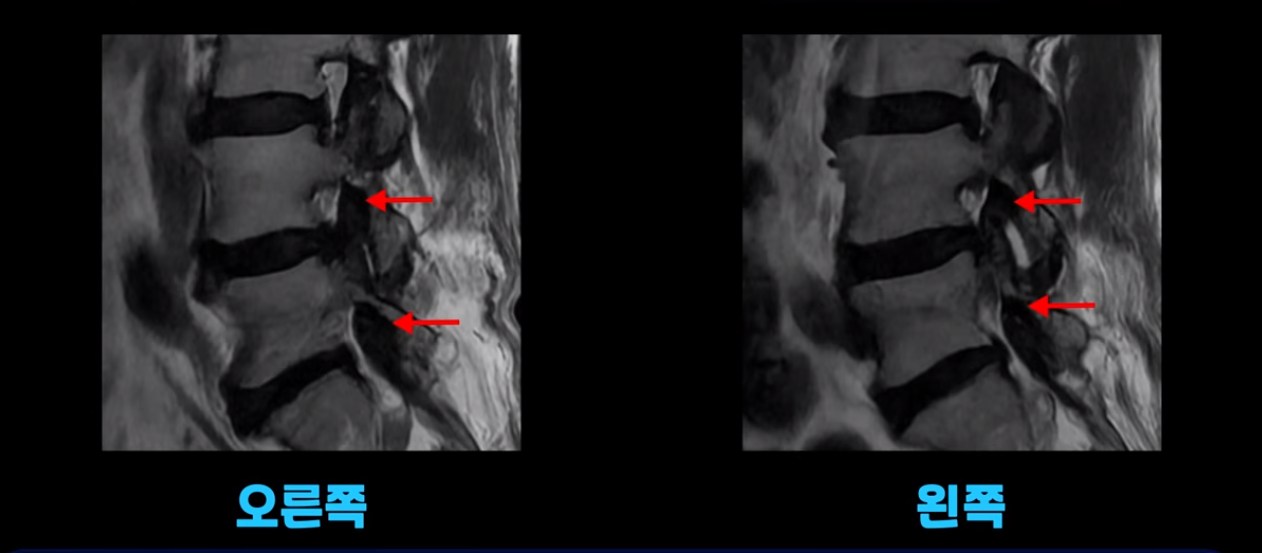

오른쪽 왼쪽 신경 가지가 나가는 추간공도 좁아져는 있지만 아주 심하지는 않습니다.

이 환자분의 가장 큰 문제는 허리를 펴는 근육인 척추기립근이 상당 부분 지방으로 변해서 하얗게 보이고 기립근의 크기도 많이 작아져 있습니다.

이 기립근은 허리를 펴주는 근육인데 이렇게 문제가 생기면 허리가 구부러집니다. 또한 이분의 근육 상태를 알 수 있는 근감소증 검사에서 중증 근감소증 진단이 나왔습니다.

이분도 중증 근감소증 진단과 함께 척추기립근이 하얗게 지방으로 변한 것이 확인되었습니다. 당연히 허리, 엉덩이, 골반, 다리 근육들은 심하게 뭉치고 굳어있었습니다. 비슷한 증상의 환자분 이야기를 더 들어보겠습니다.

이 환자분 역시 근감소증 진단을 받으셨고, 척추기립근이 심하게 지방으로 변한 게 확인됩니다. 역시 허리, 골반, 다리 근육들은 다 뭉치고 굳어있었습니다.